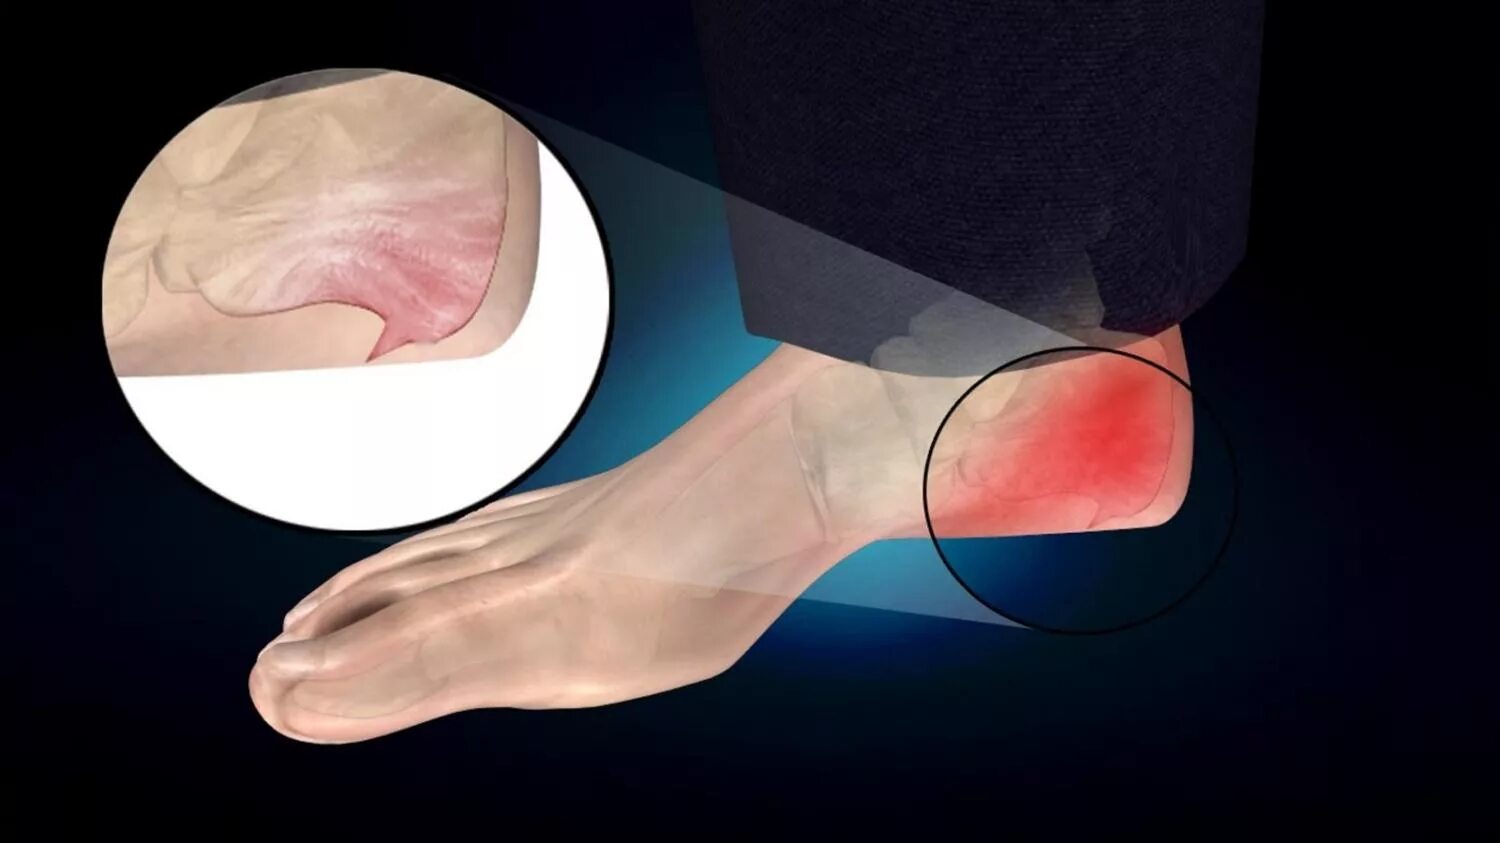

Как называется пяточная шпора